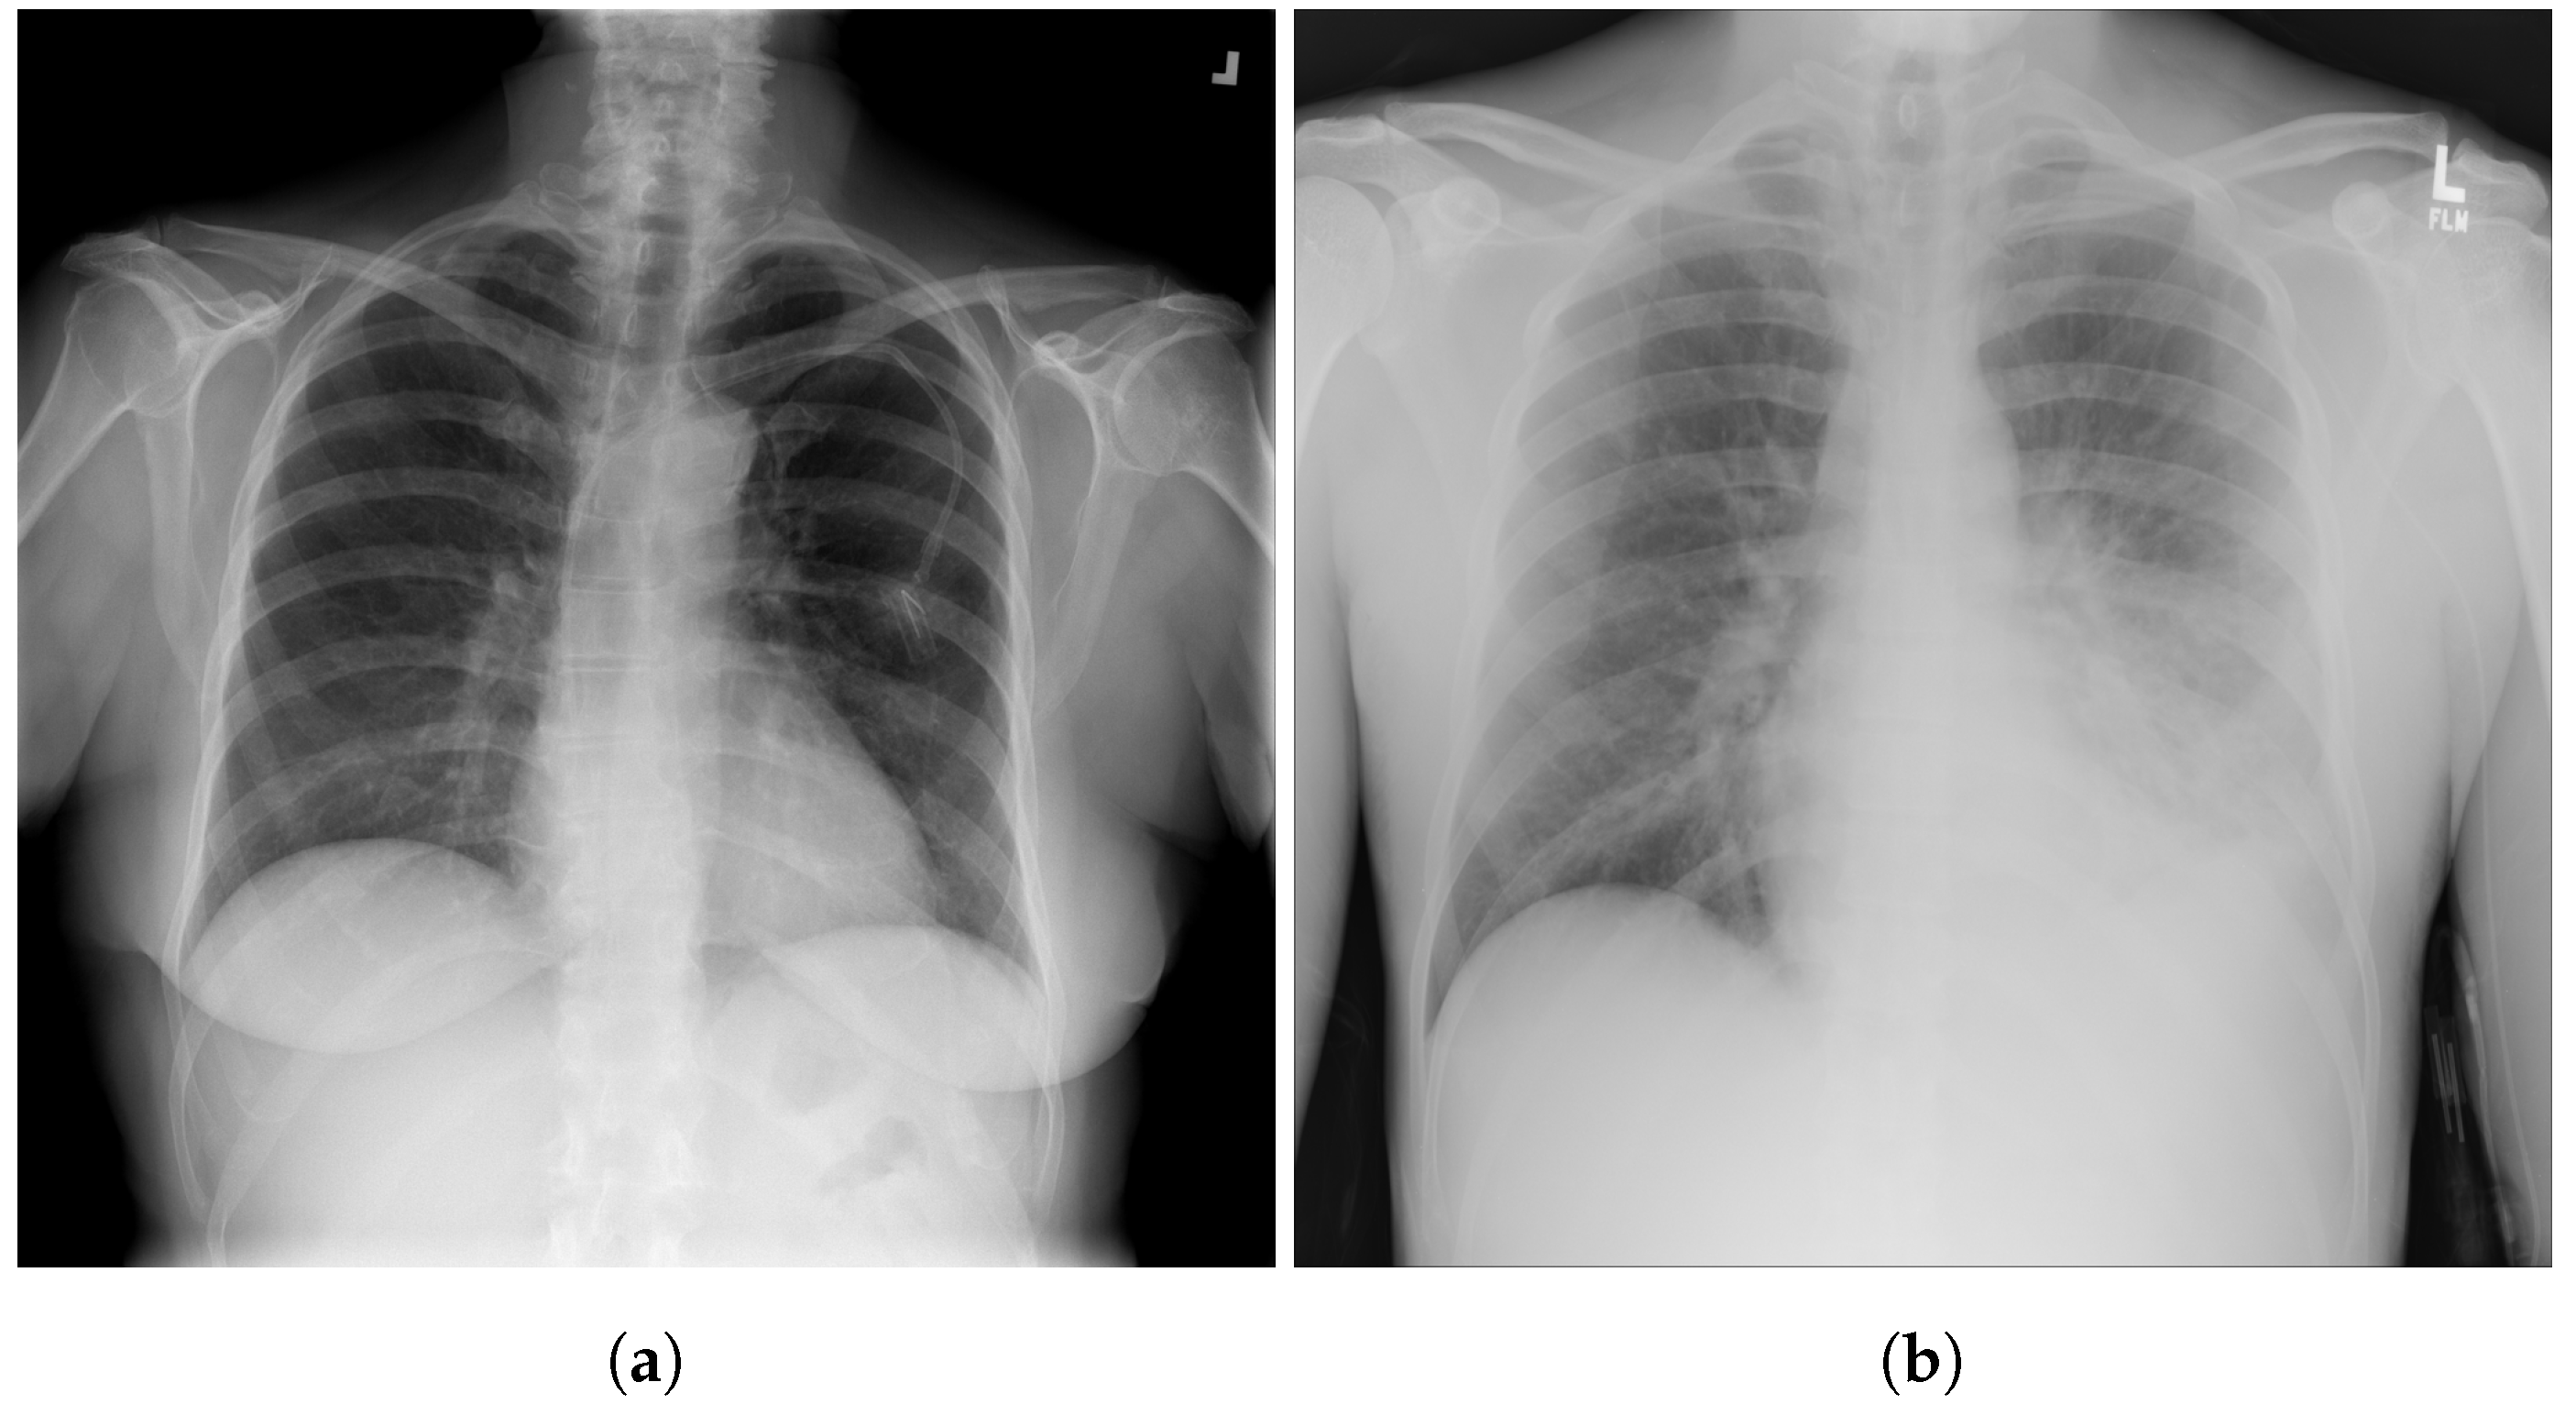

3.5. Chest X-ray Images Pneumonia (CXRIP)

3.6. Montgomery County X-ray

3.7. Shenzhen Hospital X-ray

3.8. National Institute of Health (NIH)

3.9. Montfort Dataset